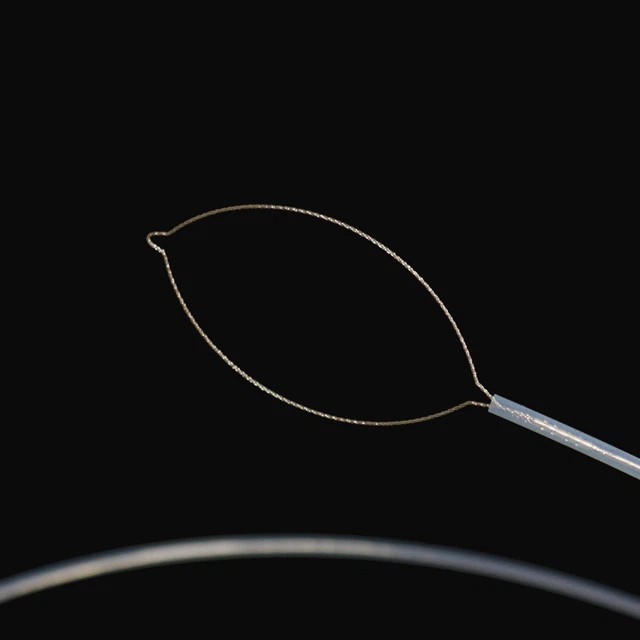

Netto tipe

|

Model |

Skede o . d . |

Werkende kanaal |

Werkslengte |

Kopwydte |

Funksies |

|

Fg -28 u -25 d2 |

2.6 |

Groter as of gelyk aan 2,8 |

2300 |

25 |

Ovaal met net |

|

Fg -28 u -30 d2 |

2.6 |

Groter as of gelyk aan 2,8 |

2300 |

30 |

Ovaal met net |